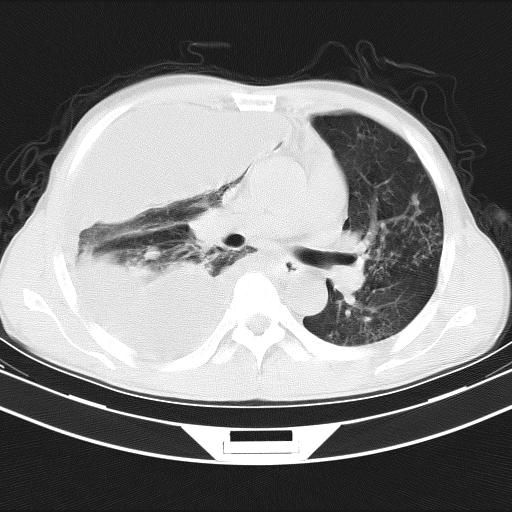

男性,44岁,结核病史多年。现胸闷气短,咳嗽,偶咳血。

右侧胸腔积液

右肺下叶不张

双肺多发结节影最分空洞形成考虑占位不除外结核

双肺陈旧性病变

1、右侧大量胸腔积液伴右肺压缩性膨胀不全,建议抽液治疗后复查 2、两肺继发性tb伴空洞形成。

1)两肺继发性肺结核伴空洞形成,左肺多发性结核球。2)右侧大量胸腔积液伴右肺部分膨胀不全。3)纵隔淋巴结肿大。